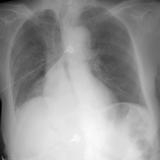

RLL Collapse 1 PA

Date: 02/28/2004

Views: 3362